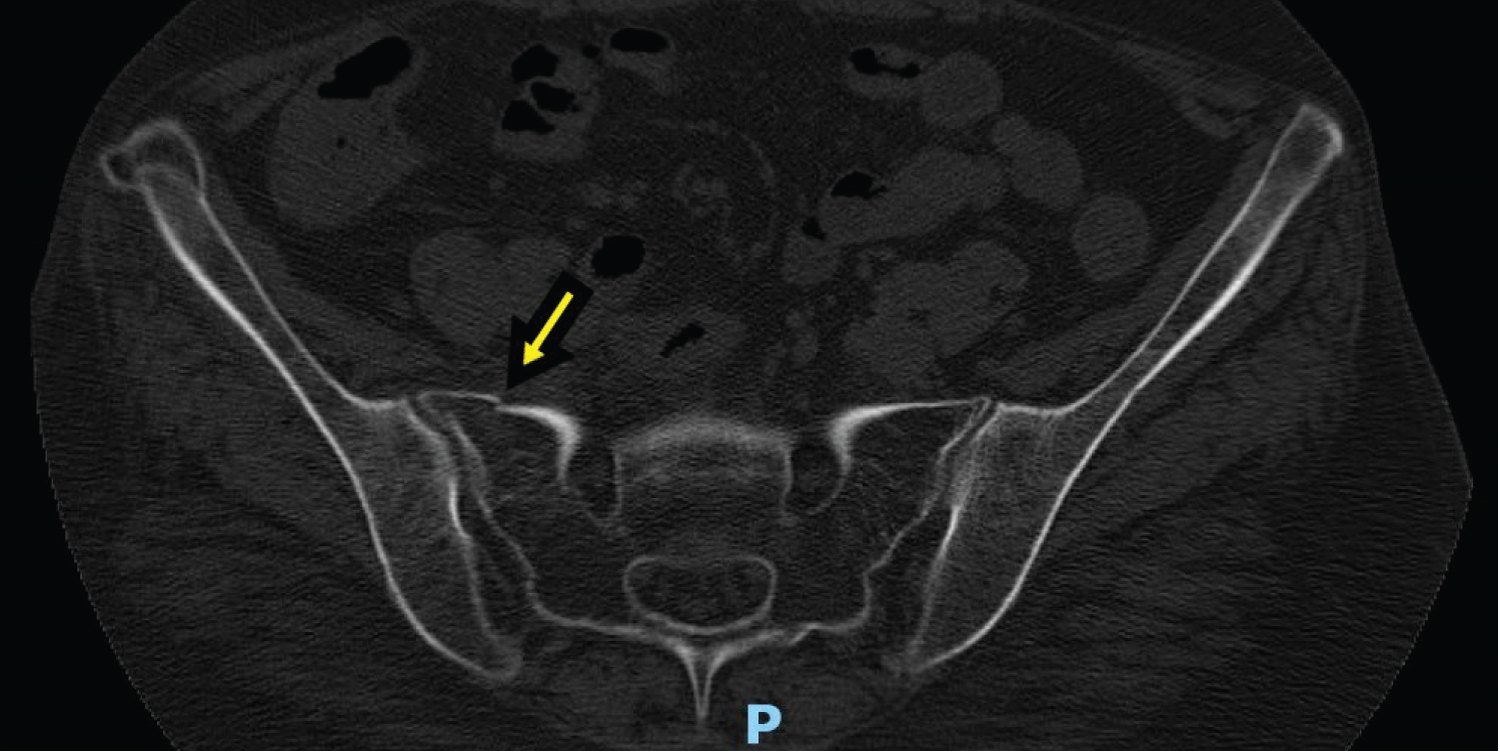

A 54-year-old African American Female presented to the ED reporting a fall after slipping on water with initial CT images of her pelvis showing a minimally displaced right sacral fracture (Figure 1 and Figure 2). The right anterior superior iliac spine changes seen on CT were previously noted on imaging from a different hospitalization. She had both an elevated Creatine Kinase (CK) (2758 U/L) and AST (411 IU/L) level. The patient was admitted for observation for 24 hours to have Orthopedic Surgery further evaluate the imaging and quality of the fracture. On further questioning of the patient, she mentioned multiple falls over the past 1-2 years requiring ED visits for fractures of various regions of her body including: right radius, left ankle, and multiple left ribs (sixth-ninth and eleventh). She reported an associated generalized weakness throughout her body, especially of her lower extremities which would lead to the falls. She reports these episodes of weakness are accompanied by pain, last for 1-2 weeks, and then self-resolve. She has noticed these episodes with stress and most recently, after a heated disagreement with a family member. On initial examination of the patient, in addition to sacral pain, she had a slightly erythematous rash around her eyes (images not available), hypopigmentation of her digits and toes, with reddish-violet colored patches over her knees (images not available), as well as macules over her metacarpophalangeal (MCP) and proximal interphalangeal (PIP) joints (Figure 3a, Figure 3b, Figure 3c and Figure 3d).

Figure 1: CT pelvis w/o contrast [Transverse View] - Inferior right pelvis partially displaced fracture 1 of 2. View Figure 1